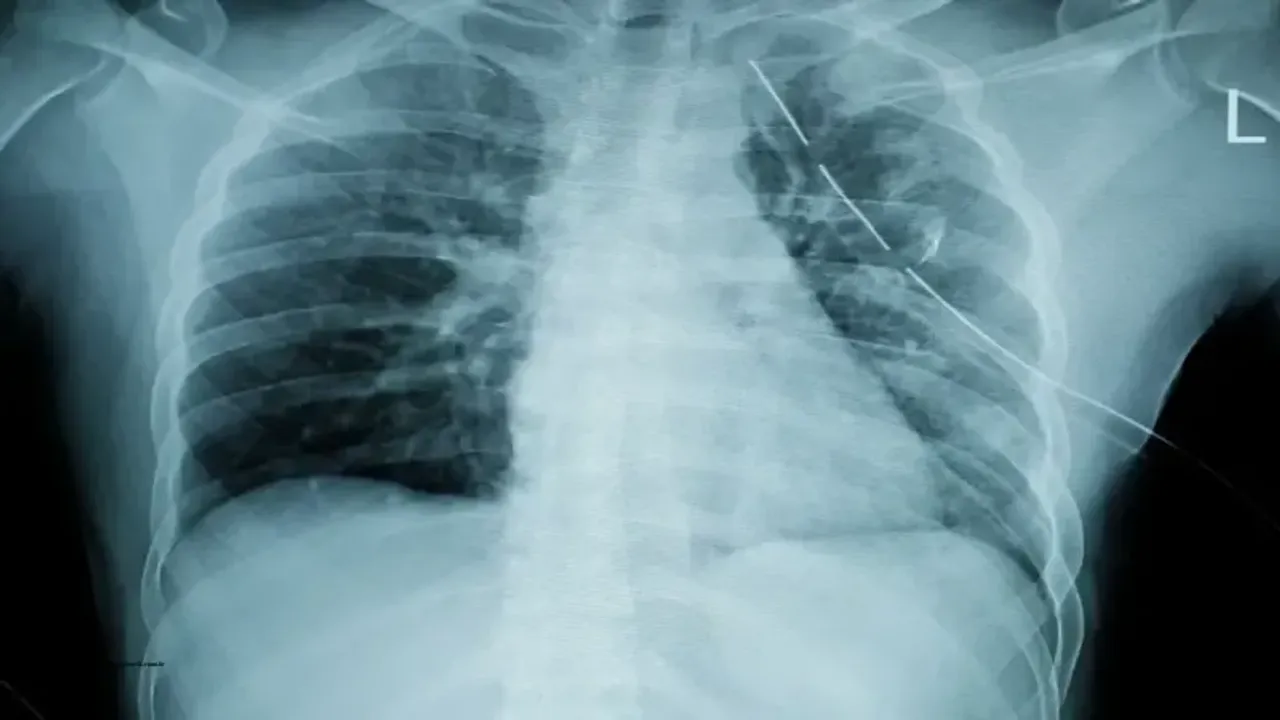

Bu belirtiler gözlemleniyorsa, kesin tanı için doktor kontrolü ve röntgen çekilmesi şarttır.

1. Röntgen ya da BT çekimi ile kırığın yeri ve şiddeti belirlenir.